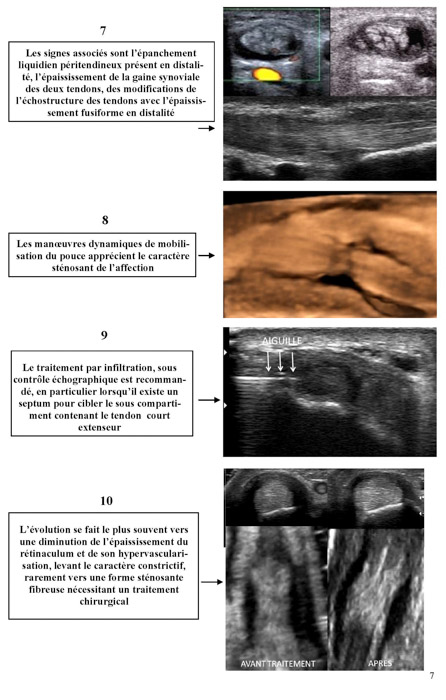

Gel Contact N°22

JUIN 2013